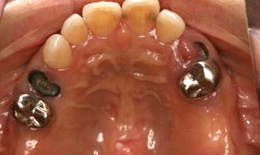

上顎

保存困難な歯を抜歯後、サイナスリフトを行いインプラントを7本埋め込んで、セラミックスクラウンを被せた